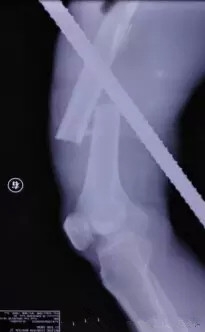

患者送到医院后,北京积水潭医院急诊医护人员迅速对患者进行心电监护、开放静脉,急配血。经X光检查,胸部的钢筋插在了胸壁上,并未伤及患者胸腔、肺部及大血管。

随后,由创伤骨科孙旭大夫主刀取另外一根钢筋。这根钢筋是从右腿后侧插入体内后从前方穿出,造成患者股骨干骨折,但幸运的是钢筋的走势虽然离重要的血管特别近,但是并未伤及。为了减小二次伤害,孙旭大夫决定采取直接将钢筋拔出的手术方案。

孙旭大夫摸着患者的足背动脉搏动将钢筋从大腿中一点点撤出。在钢筋走形的路径里,采用了外科专用的清洗设备进行伤口清理和清创,同时进行了骨折复位。孙大夫考虑内固定架可能会引起伤口感染风险,于是采用了外固定架,手术持续了近两个小时,顺利完成。患者的生命保住了。